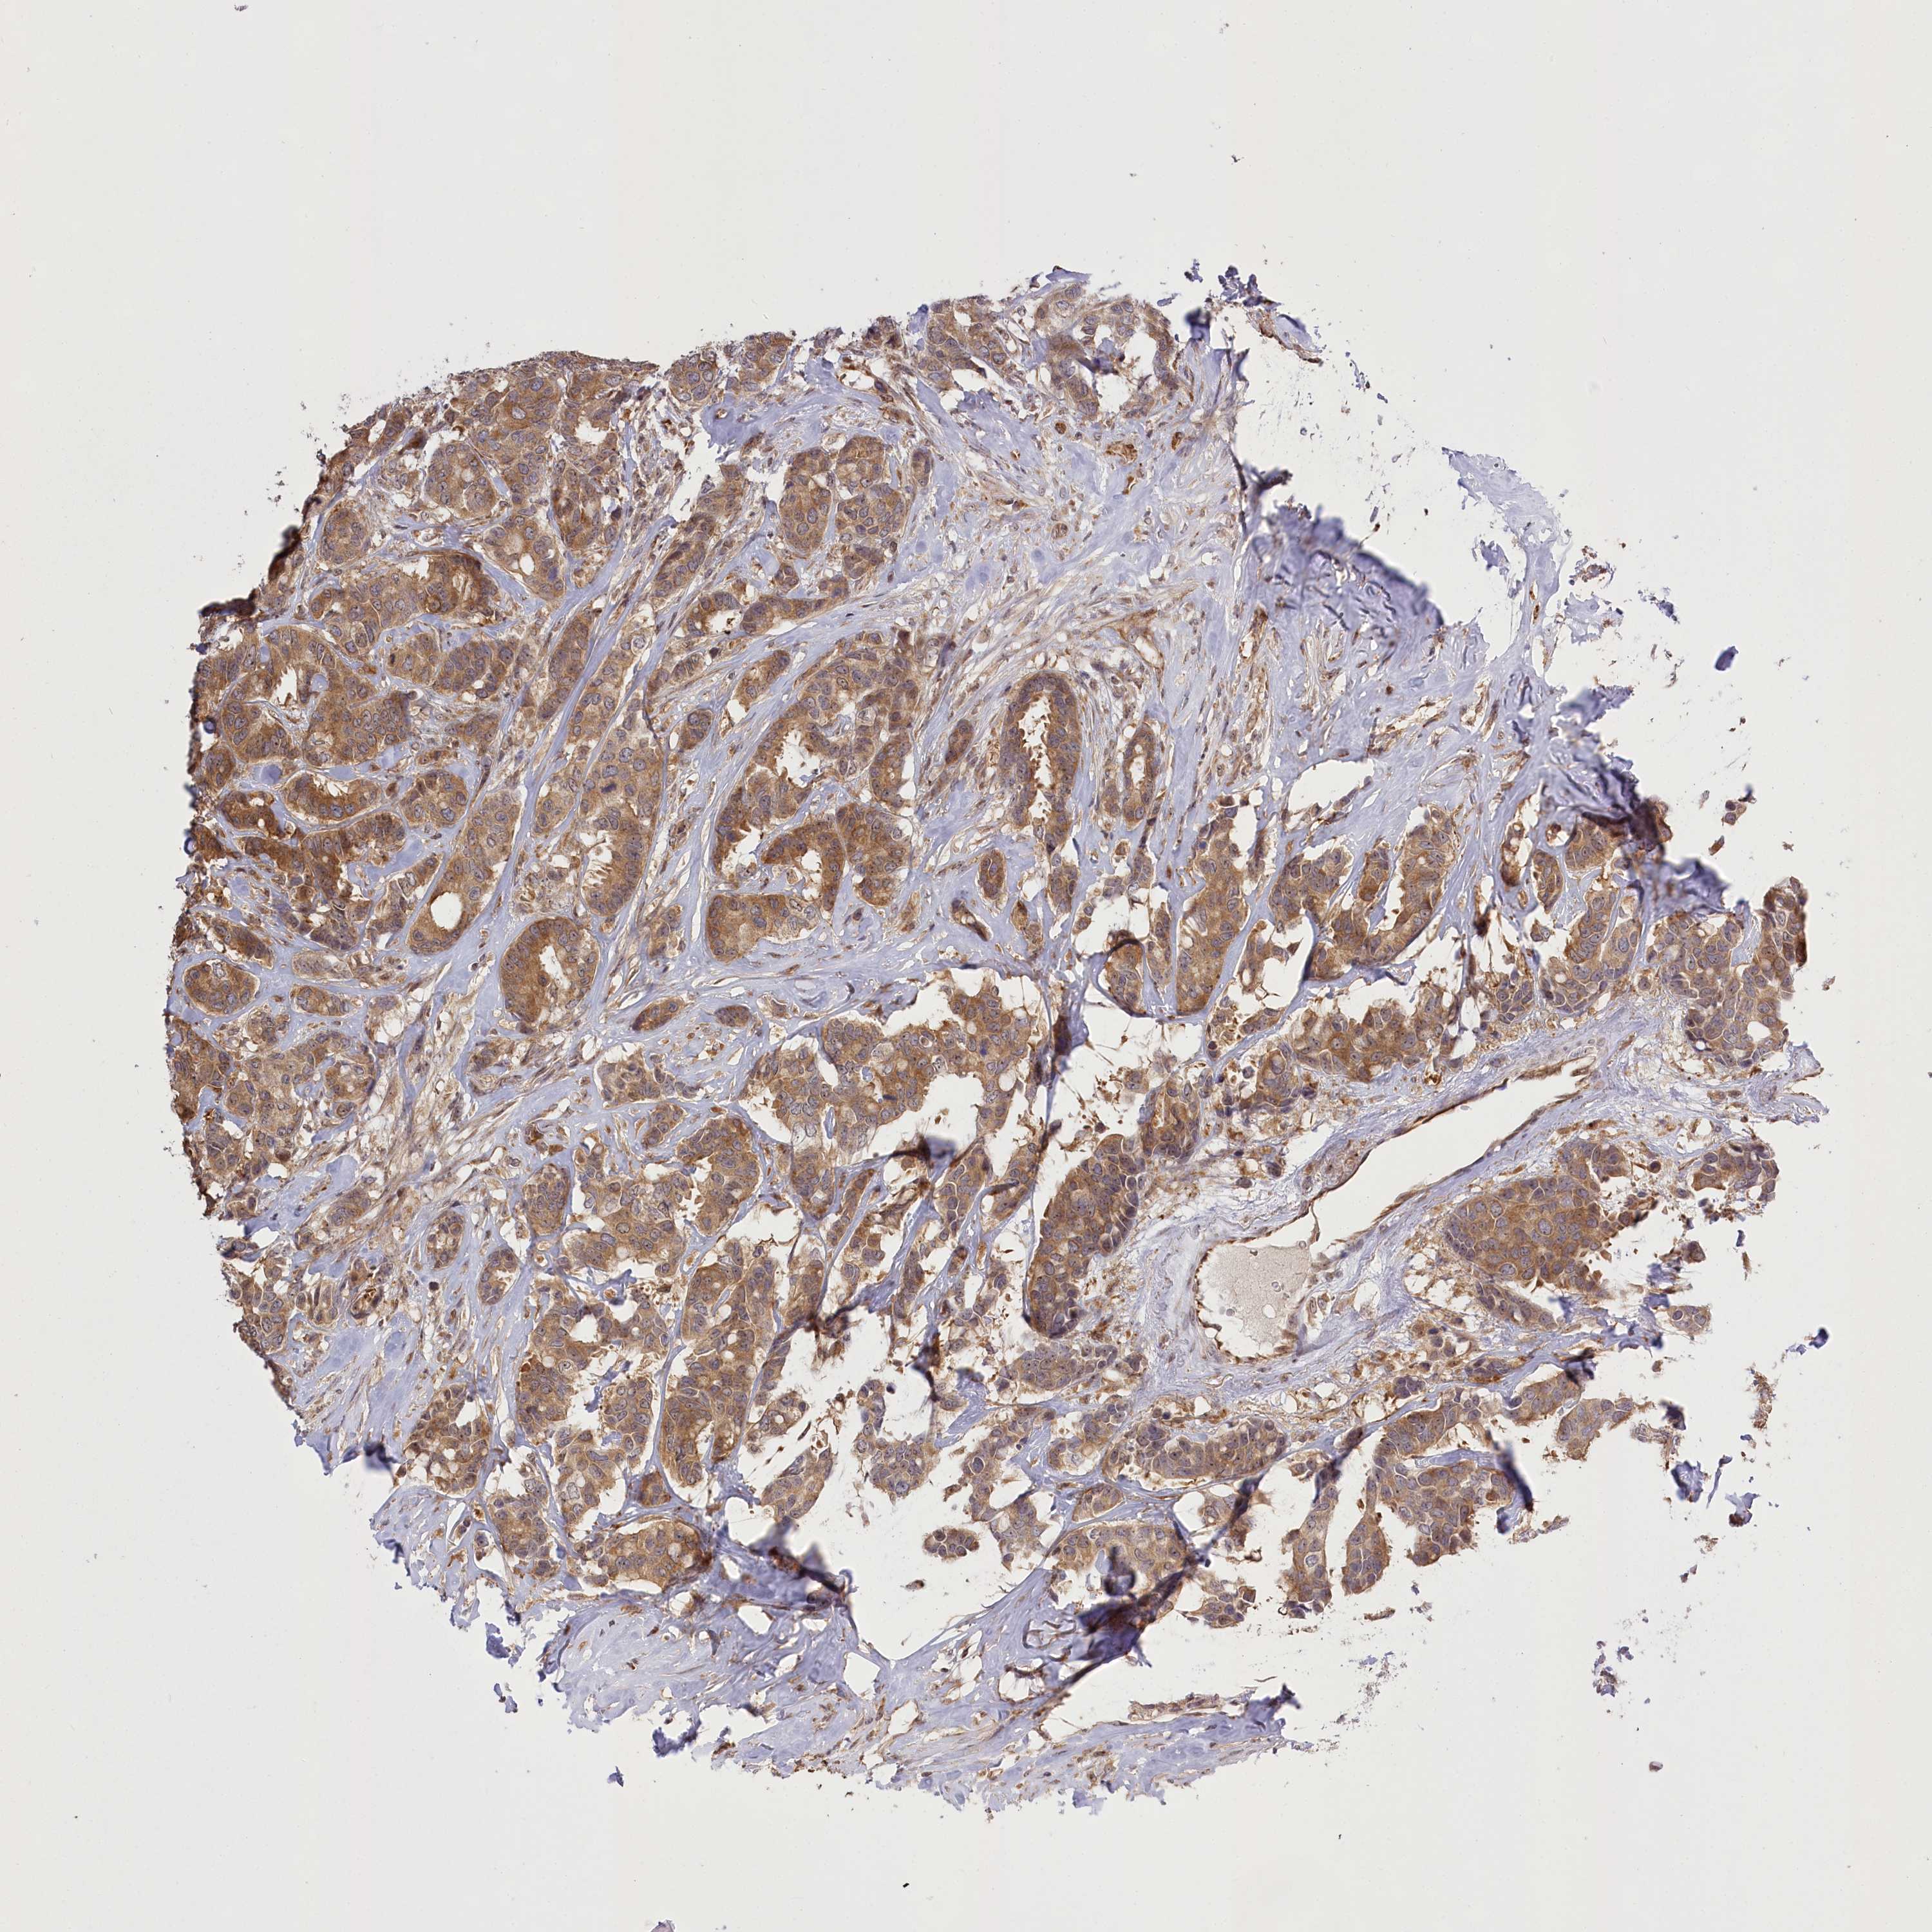

CANCER BREAST CANCER Show tissue menu

BRCA TCGA BRCA VALIDATION PROTEIN EXPRESSION